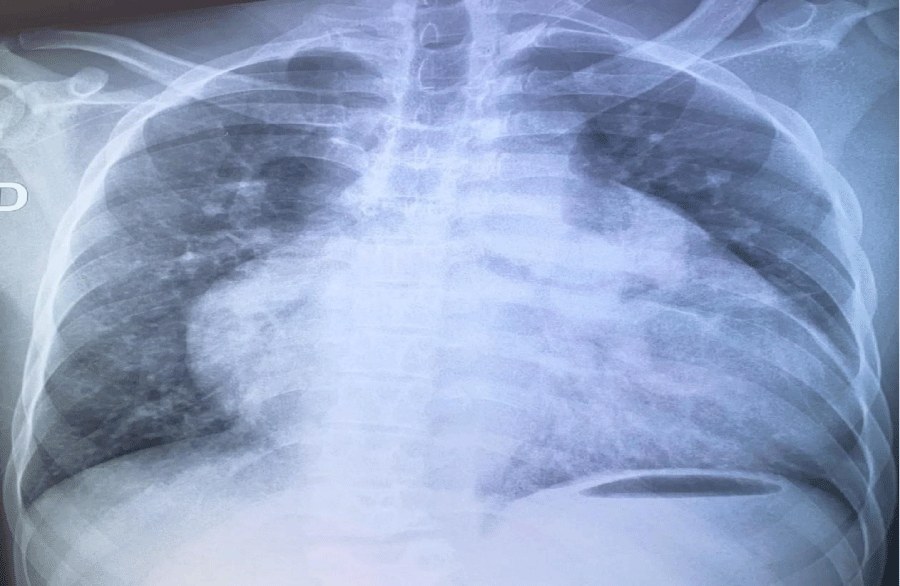

Biological tests showed polycythemia of 7 million/ul and mild anaemia of 11g/dL. The electrocardiogram showed atrial fibrillation (AF) with rapid ventricular response, while the X-ray showed significant cardiomegaly. Echocardiography showed a short-axis parasternal slice centred on the PA, with a tripod image and a left-right shunt between the aorta and PA. Continuous Doppler showed systolic flow in this shunt with diastolic extension without return to the isoelectric line. There was a passage of air bubbles into the left cavities (the patient had a venous line), dilatation of the coronary sinus, dilatation of the right cavities, and severe PAH at 90 mmHg. Echocardiography concluded that the patient had PCA with severe right-sided dilatation and severe PH associated with abnormal venous return. Chest CT showed the existence of two superior vena cava, one on the left and the other on the right, draining into the left and right atria respectively.

The patient was a 27-year-old mechanic with no known cardiovascular risk factors. He was admitted for syncope of sudden onset with no prodromal symptoms or associated signs. The patient had been suffering from permanent palpitations and exertional dyspnoea for several months. On physical examination, consciousness was clear, with blood pressure at 124/74 mmHg, tachycardia at 133 beats per minute and xiphoid tingling. Auscultation revealed irregular heart sounds with a tricuspid insufficiency murmur of intensity 4/6 and an aortic insufficiency murmur of intensity 3/6. Examination of the other equipment was normal. The electrocardiogram showed coarse-mesh atrial fibrillation with a rapid ventricular response of 140 cycles per minute (Figure 1). The chest X-ray showed cardiomegaly (cardiothoracic index = 0.75), a right inferior arch protrusion (dilatation of the right atrium), and a convex middle arch with an outward point (Figure 2). On Doppler echocardiography, there were visible bullae in the left cavities, significant dilatation of the right cavities, persistence of the ductus arteriosus, pulmonary hypertension (PAPS= 90 mmHg) and major dilatation of the coronary sinus in favour (Figure 3). The CT-scan also showed dilation of the right cavities and confirmed the presence of two superior vena cava, one on the right draining into the right atrium and the other on the left draining into the coronary sinus (Figure 4). The biology work-up showed polycythemia at 7 million/ul and mild anaemia at 11g/dL. The diagnosis was persistent CA and SCAV complicated by AF. The patient was treated with a curative dose of Enoxaparin followed by Rivaroxaban and Amiodarone. The course was marked by the onset of cardiovascular collapse refractory to vasopressive amides, followed by death on the seventh day of hospitalisation.